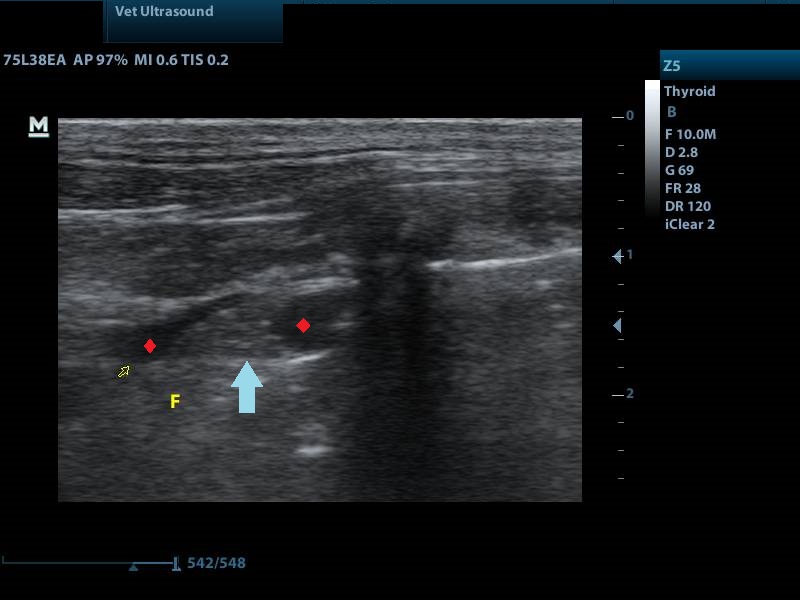

Ευρήματα: Στον υπέρηχο κοιλίας δεν υπήρχαν ευρήματα για αυτό τον λόγο συνεχίστηκε η εξέταση και στη θωρακική κοιλότητα ώστε να βρεθεί η αιτία των αυξημένων λευκών αιμοσφαιρίων ( στοιχείο που συνήθως δείχνει πως υπάρχει κάποια συλλογή, εφόσον έχουν αποκλειστεί άλλα αίτια). Η καρδιά ελέγχθηκε φυσιολογική σε ηχοδομή και λειτουργικότητα. Στη διάρκεια της εξέτασης της καρδιάς η περιοχή γύρω από αυτήν και μεταξύ των λοβών του πνεύμονα ήταν αρκετά υπερηχογενής. Στα πρόσθια πνευμονικά πεδία ανιχνεύθηκε μικρή συλλογή υγρού η οποία και παρακεντήθηκε. Στη συνέχεια έγινε ακτινογραφία θώρακος για να εκτιμηθεί η κατάσταση του πνευμονικού παρεγχύματος και της θωρακικής κοιλότητας. Στην ακτινογραφία βρέθηκε πως οι κορυφές των οπίσθιων λοβών του πνεύμονα δεν ήταν οξύληκτοι στοιχείο που μας δείχνει πως πιθανότατα έχει αναπτυχθεί ινώδης ιστός μεταξύ των λοβών και του υπεζωκότα. Εικόνα χρόνιας φλεγμονής. Έγινε λήψη του υγρού όπου δεν βρέθηκαν μικροοργανισμοί αλλά αφθονία ουδετερόφιλων και μακροφάγων κυττάρων. Λαμβάνοντας όλα τα ευρήματα υπ’ όψιν καταλήγουμε στο συμπέρασμα πως πρόκειται για μια χρόνια άσηπτη φλεγμονή του υπεζωκότα η οποία είναι παραγωγική. Σε περίπτωση που υπάρξει ξανά συλλογή μπορεί να γίνει πλευροδεσία με ενδοθωρακική χορήγηση ιωδιούχου τάλκ. Η τεχνική αυτή εφαρμόζεται σε χρόνιες πλευρίτιδες κυρίως από νεοπλασματικά αίτια.

μπλε βέλος: λοβός του πνεύμονα

αστερίσκοι: υγρό ( μαύρο)

μπλε βέλος: ακουστική σκιά από τις πλευρές

κόκκινο βέλος: υγρό

μπλε γραμμή: αφορίζει το πνεύμονα προς τα κάτω